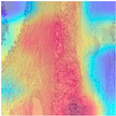

| Image Class | BreakHis Dataset(40×) | |||

| Benign | Malignant | |||

| Original images |  |  |  |  |

| MFF-ClassificationNet heatmaps |  |  |  |  |